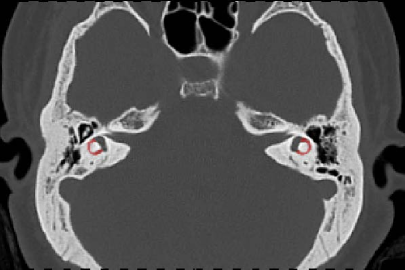

Annotation of the lateral semicircular canal plays an important role in the automatic calibration method of the raw temporal bone CT image. However, large-scale medical image data annotation is expensive and difficult to obtain. Therefore, we proposed an LSC segmentation algorithm to roughly predict the location of anchors. The lateral semicircular canal is a small sophisticated anatomical structure in the temporal bone. It is a semicircle canal that embedded in the temporal bone. In a CT volume, a lateral semicircular canal contains about 200 to 300 voxels. In different observation positions, the LSC vary greatly, as shown in Figure 2, which also makes it difficult to segment accurately.

Refer to caption

(a) Transverse position

(b) Coronal position

(c) Sagittal position

Figure 2: The LSCs in different views.